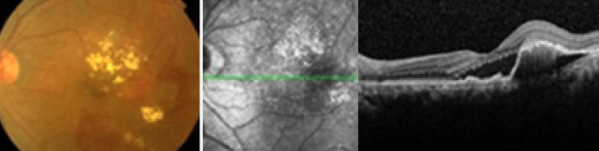

안저촬영 및 빛간섭단층촬영에서 보이는 습성 황반변성

망막 아래 맥락막에서 새로운 혈관이 생겨 출혈이나 삼출물이 나오게 되면

습성 황반변성이 됩니다.

레이저 광응고술, 광역학요법 등을 이용한 치료가 필요합니다.